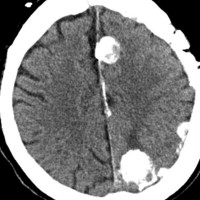

片側髄膜腫症 unilateral meningiomatosis

50歳ころから15年間に3回の開頭手術を受けている患者さんです。parasagittal, falx, convexityなど6個の髄膜腫がすでに摘出されています。左側だけ,テント上だけに髄膜腫が20個くらい多発していました。これらはグレード1で,anaplastic meningiomaの転移ではありません。

やがて蝶形骨縁の髄膜腫の増大速度が早まりatypical meningiomaとなりました。MIB-1 index が10%の高値でした。病理学的にも,psamomatous meningiomaなど様々な種類の髄膜腫が多発しています。

初発時から多発性髄膜腫であり,最初の手術で左側テント上の硬膜を広範囲に摘出しておくべきでした。このような病態は若年者でもみられることがあり,胎生期の硬膜の原基になる細胞にmutationが生じたとしか考えづらいものです。